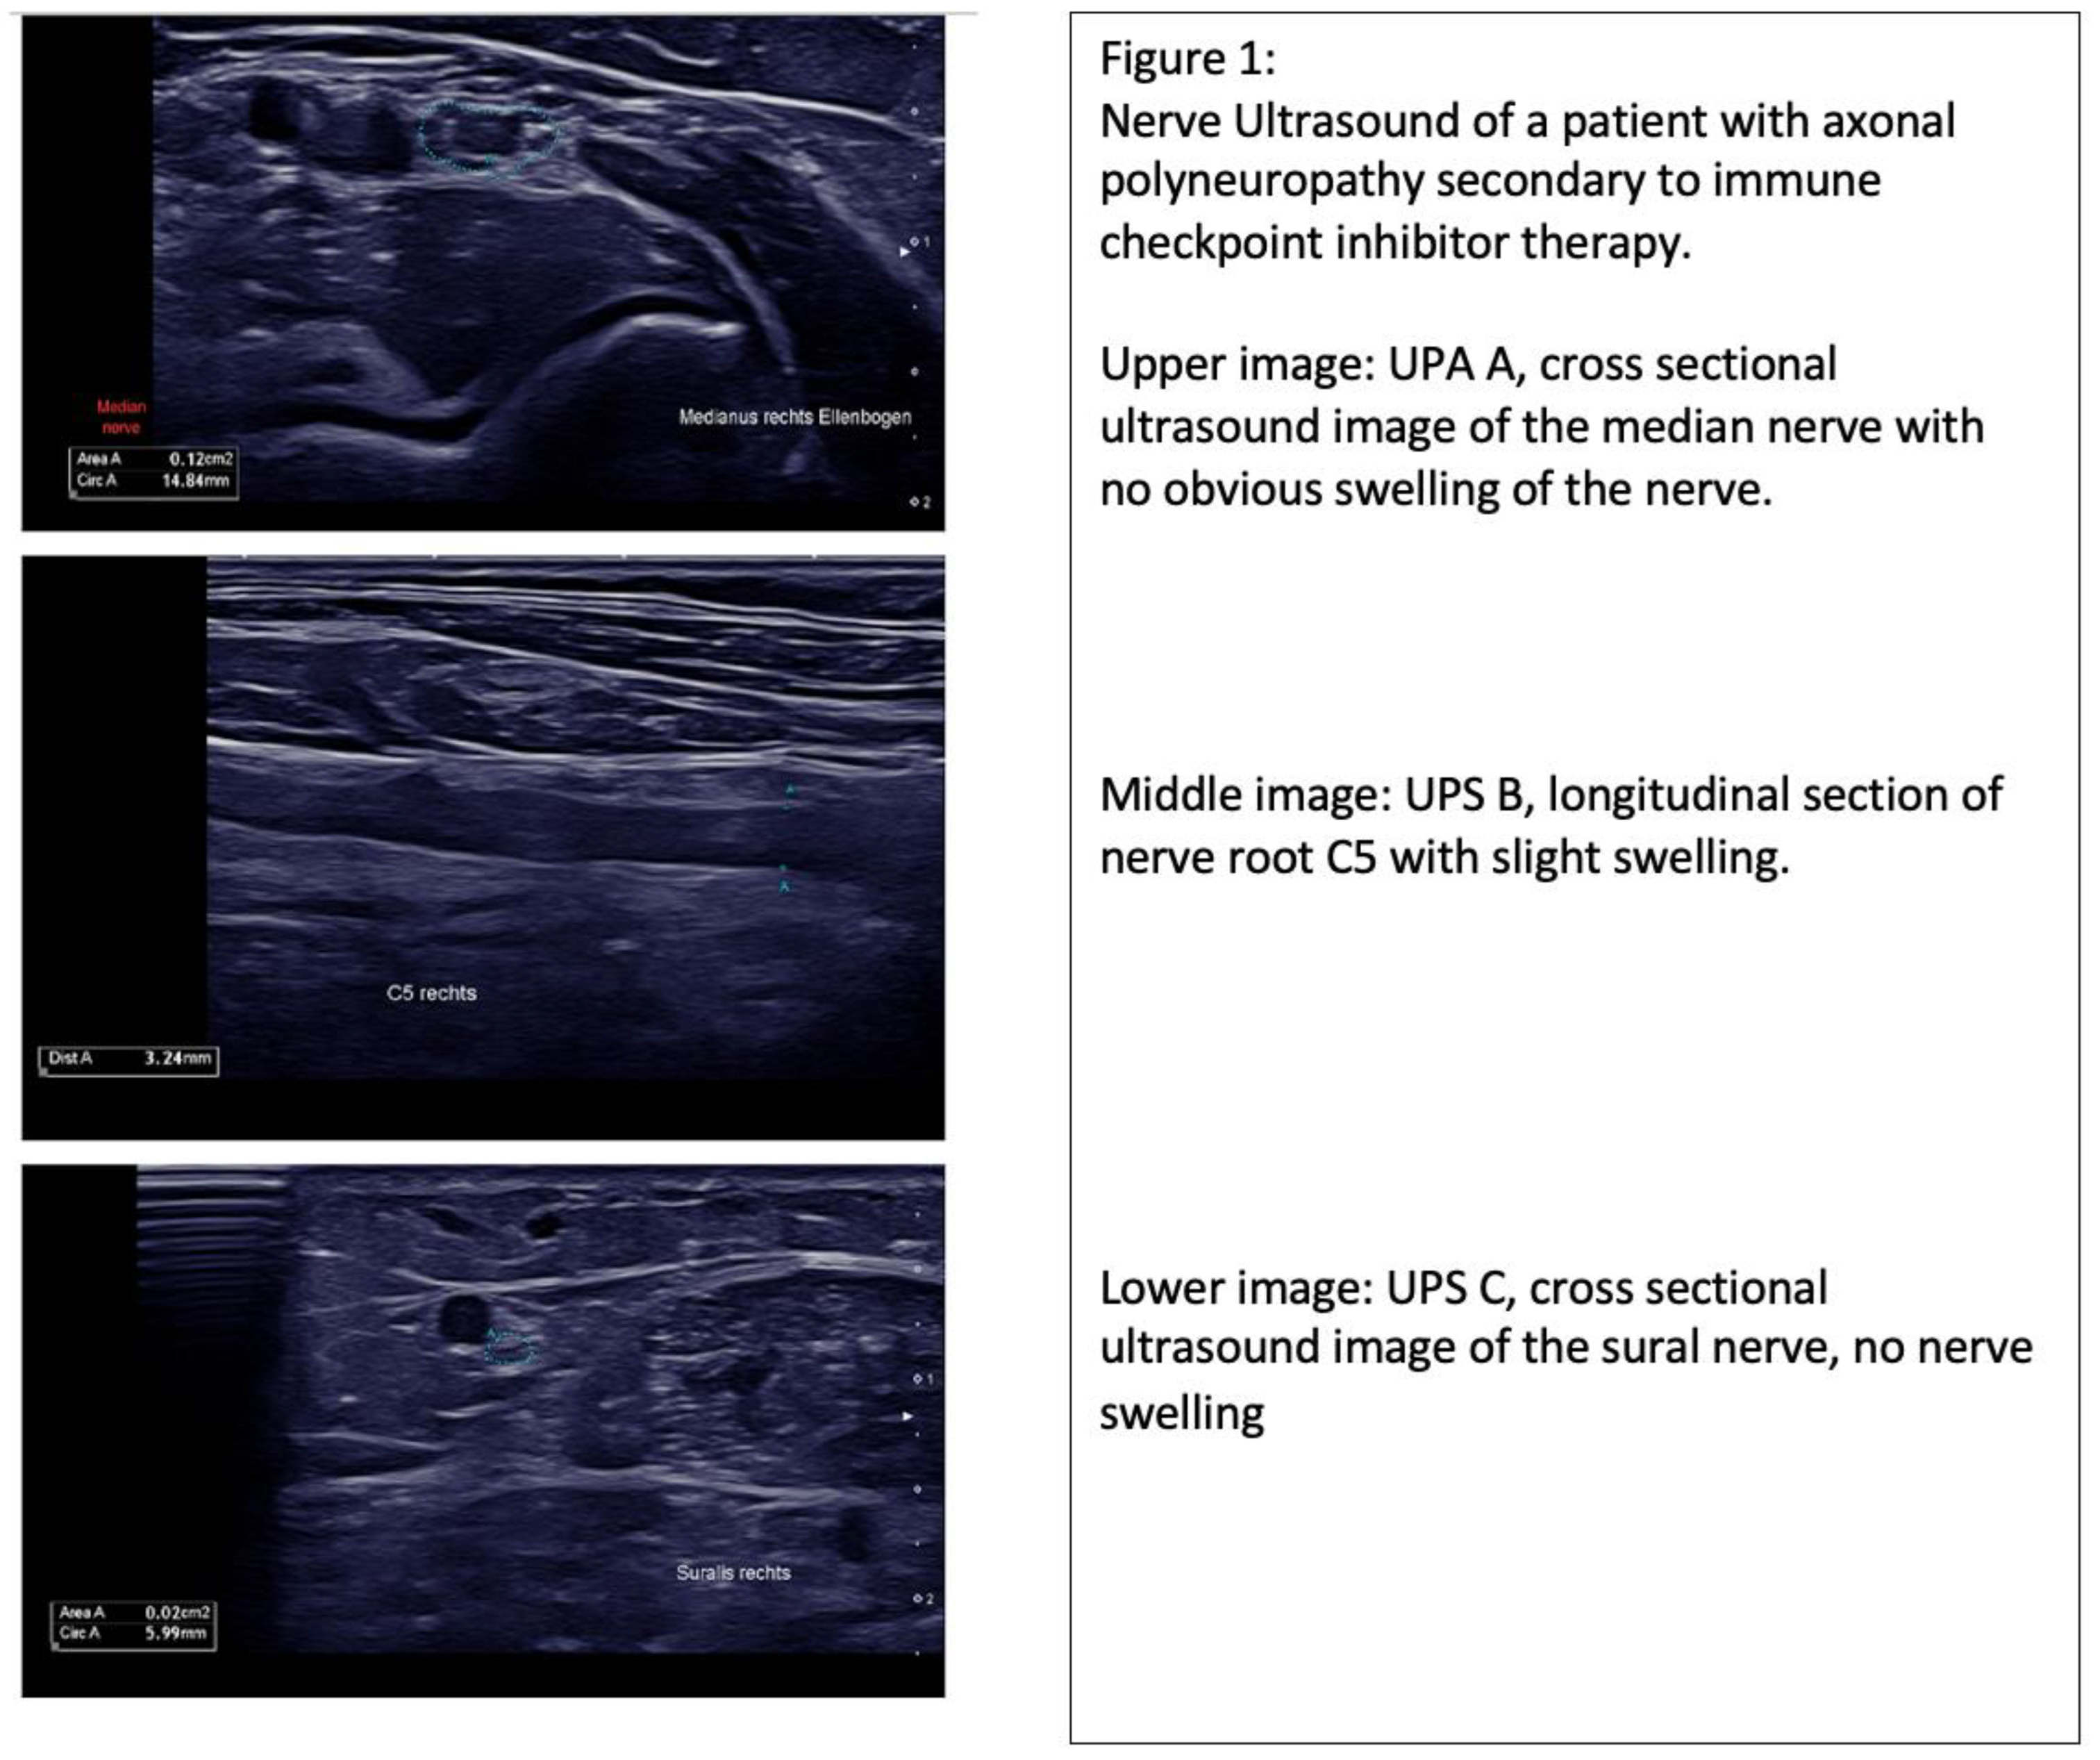

In our patient collective, 60% of cases showed nerve swelling, which was inhomogenic and did not solely affect the peripheral sensorimotor nerves (UPS A), but also affected the C5/6 nerve roots, vagus nerve (UPS B) and sensory nerves (UPS C). In 20% of patients no nerve swelling was observed, and the UPSS obtained varied from 0 to 5. (Table 1, Figure 1).

Figure 1.

Nerve sonography data of (top) patient with immunotherapy-related adverse event; (middle) patient with chemotherapy-associated polyneuropathy; (bottom) patient with chronic inflammatory demyelinating polyneuropathy. Abbreviations: UPS A (Ultrasound Pattern Score A): peripheral sensorimotor nerves; UPS B (Ultrasound Pattern Score B): C5/6 nerve roots and vagus nerve; UPS C (Ultrasound Pattern Score): sensory nerves.

Nerve ultrasound in CIDP patients may reveal prominent single-fascicle swelling or increased intraneural echogenicity. The current data suggest that increased nerve echogenicity is associated with nerve structure remodeling, which is secondary to chronic inflammatory processes. Further, nerve swelling may affect all nerve segments, which was also found in our CIDP cohort. Compared to our CIDP patient collective, the nerve swelling observed in our nirAE patients was slight and not statistically significant, with p > 0.05. (Table 2, Figure 1). Although increased nerve swelling and, therefore, an increased UPSS is observed in patients with autoimmune-mediated polyneuropathies, there are exemptions to this as seen in sarcoidosis or vasculitis.